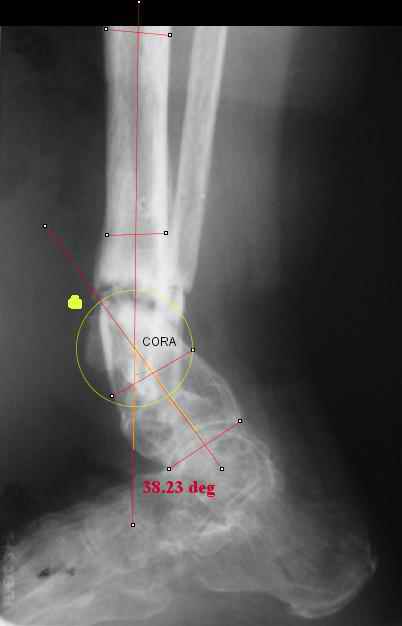

TDVC> I played with your image using some orthopedic software

TDVC> we have been developing for digital image analysis.

TDVC> a correction around the CORA through the old # will restore

TDVC> alignment without much translation.

Re the CORA.:

I think that if you locate the hinge at that site and then you rotate the foot about this point with out distraction you will be perfectly lined up. If you distract in the axis of the proximal tibia then rotate, it should still work (the hinge should still be located in the mid tibial axis). But, if you distract out of that axis then you will get translation. Does that make sense?

I looked at your image. I presume your yellow marker is the hinge axis? I think this should be at the CORA.